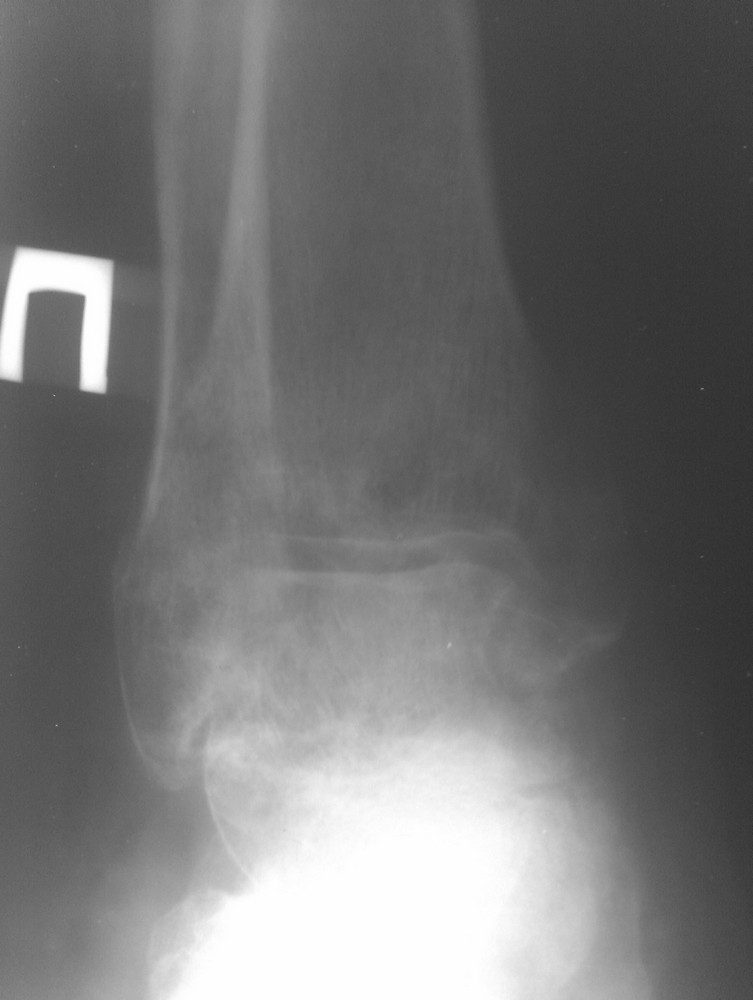

Консолидированные в неправильном положении мыщелки ББК |

Травма от июля 2011 года, лечили консервативно гипсовым тутором (про травму лодыжек - не помнит или не знает). Через 2 недели после травмы - легочная эмболия и илеофеморальный тромбоз, находился на стац лечении. После теоретического сращения мыщелков и снятия гипсового тутора разработка движений безрезультативна, опорности конечности нет. Со слов - прыгает на костылях до самого настоящего момента.

Сейчас - боль, передний ящик, люфт при нагрузке на ВБС. Боль в области внутренней лодыжки. Движения в голеностопе 5-0-15, в коленном суставе - 0-0-10, болезненные. При попытке встать полным весом и сделать шаг - нестабильность, ногу подворачивает.